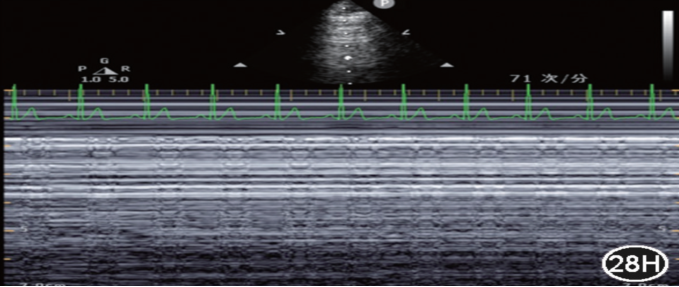

图17为肺超(低频凸阵探头),经腋中线做垂直肋骨的M型超声下可见“肺搏动征”。

图片